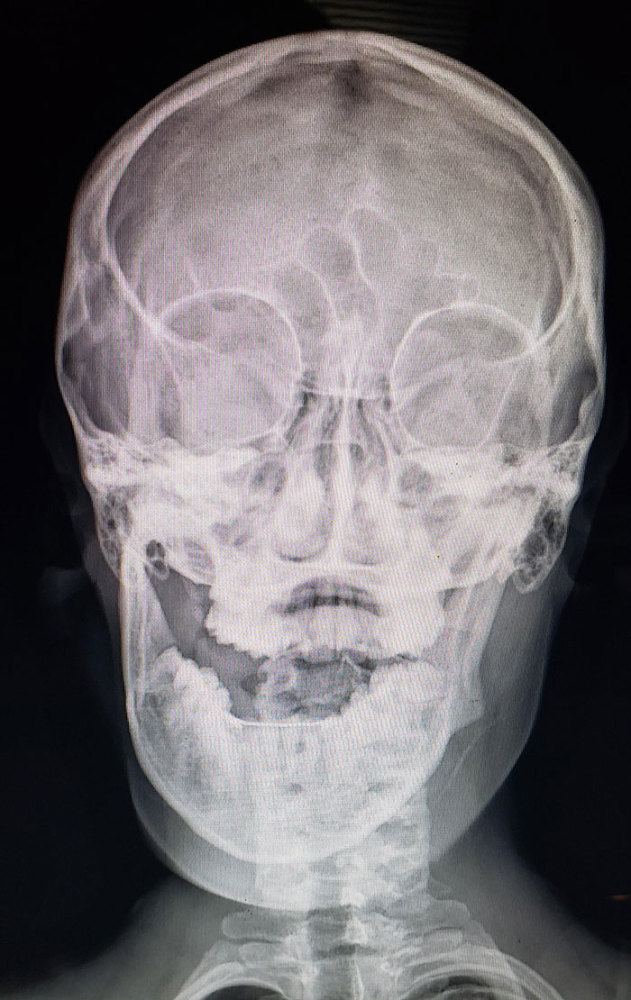

文章插图

我下颌脱臼了